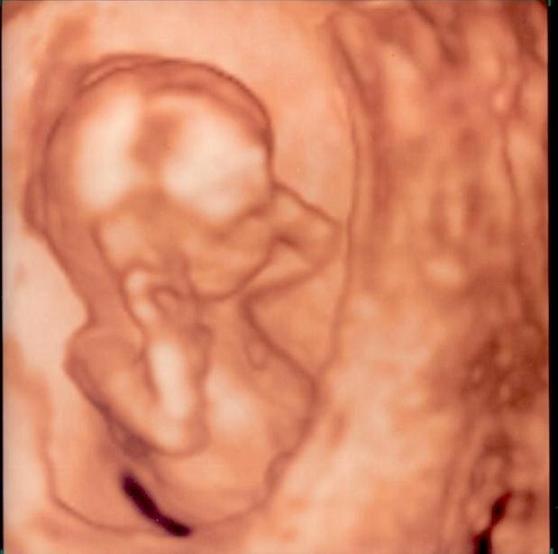

Szisszka- Micsoda szépséges kis emberpalánta

Csodaszép a picikéd

Csodaszépséges a kisasszony